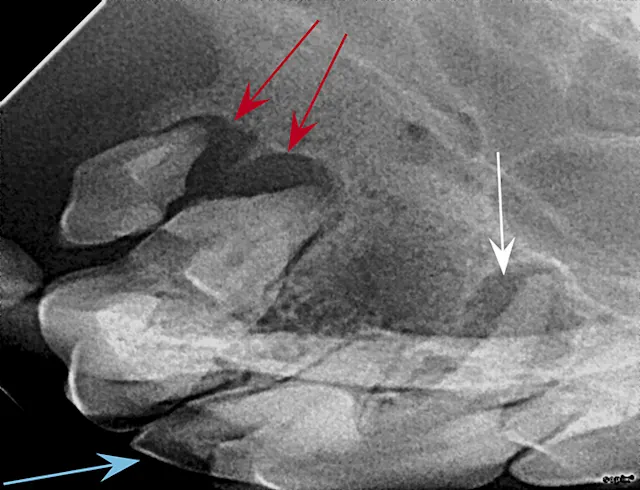

FIGURE 1: Periapical lucency

Periapical lucency develops secondary to bone loss around the tooth root caused by endodontic, neoplastic, or periodontal disease. In this dog, periapical lucency of the maxillary first and second molars (red arrows) developed secondary to periodontal disease. Periapical lucency secondary to endodontic disease (caused by exposure of the pulp from a slab fracture [blue arrow]) is also present surrounding the roots of the right maxillary fourth premolar (white arrow).

Observation of marked mobility of the molars would be expected on anesthetized examination. In this dog, the maxillary fourth premolar would likely not be mobile, as there is still bone surrounding the root apices. Extraction of the maxillary fourth premolar and first and second molars is indicated.